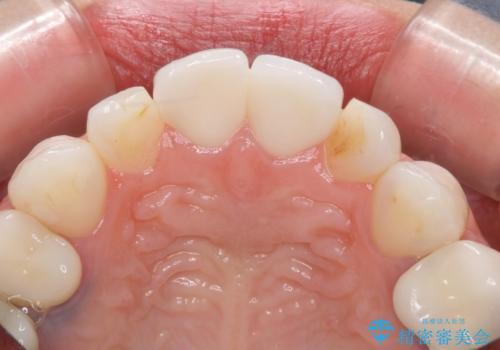

ラミネートベニヤの破折 ジルコニアクラウンによるやり替え

- 欠けてしまった前歯のラミネートベニヤと見た目の改善を求めて来院されました。

歯の大きさの不揃いと、虫歯の再発を認めたためラミネートのやりかえではなく一挙に問題の解決のできるジルコニアクラウンでの治療を計画します。

歯の大きさの不揃いが改善されただけでなく、色調もよくなり審美性をしっかりと改善することができました。